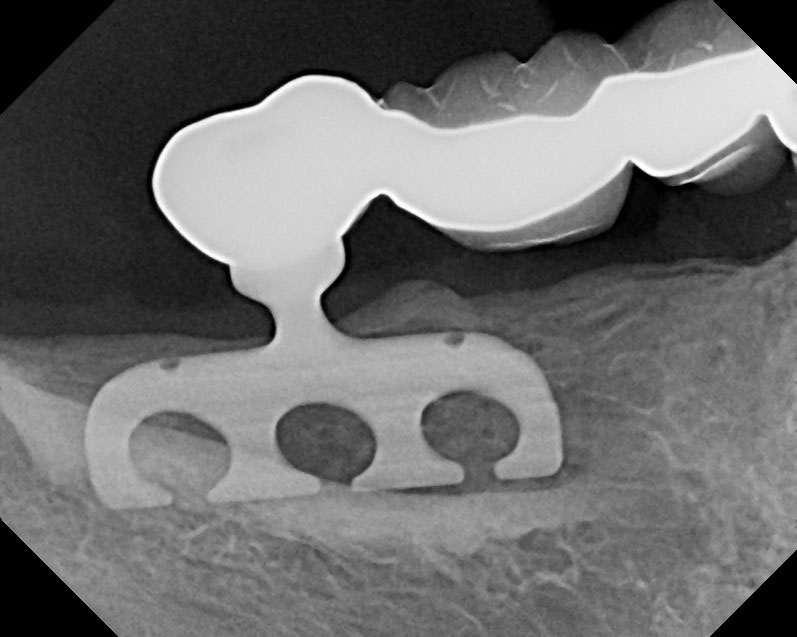

Figure 42 – Radiograph of a fractured posterior implant.

Figure 42

Figure 43 – Gingiva incised and a trephine drill used to remove the fractured implant.

Figure 43

Mechanical complications include loosening of screws, fractured screws, and even fractured implants due to force overload. However, the incidence of fixture fracture has been reported to be less of an issue than that of tooth fracture13 (Figure 42 through Figure 43).